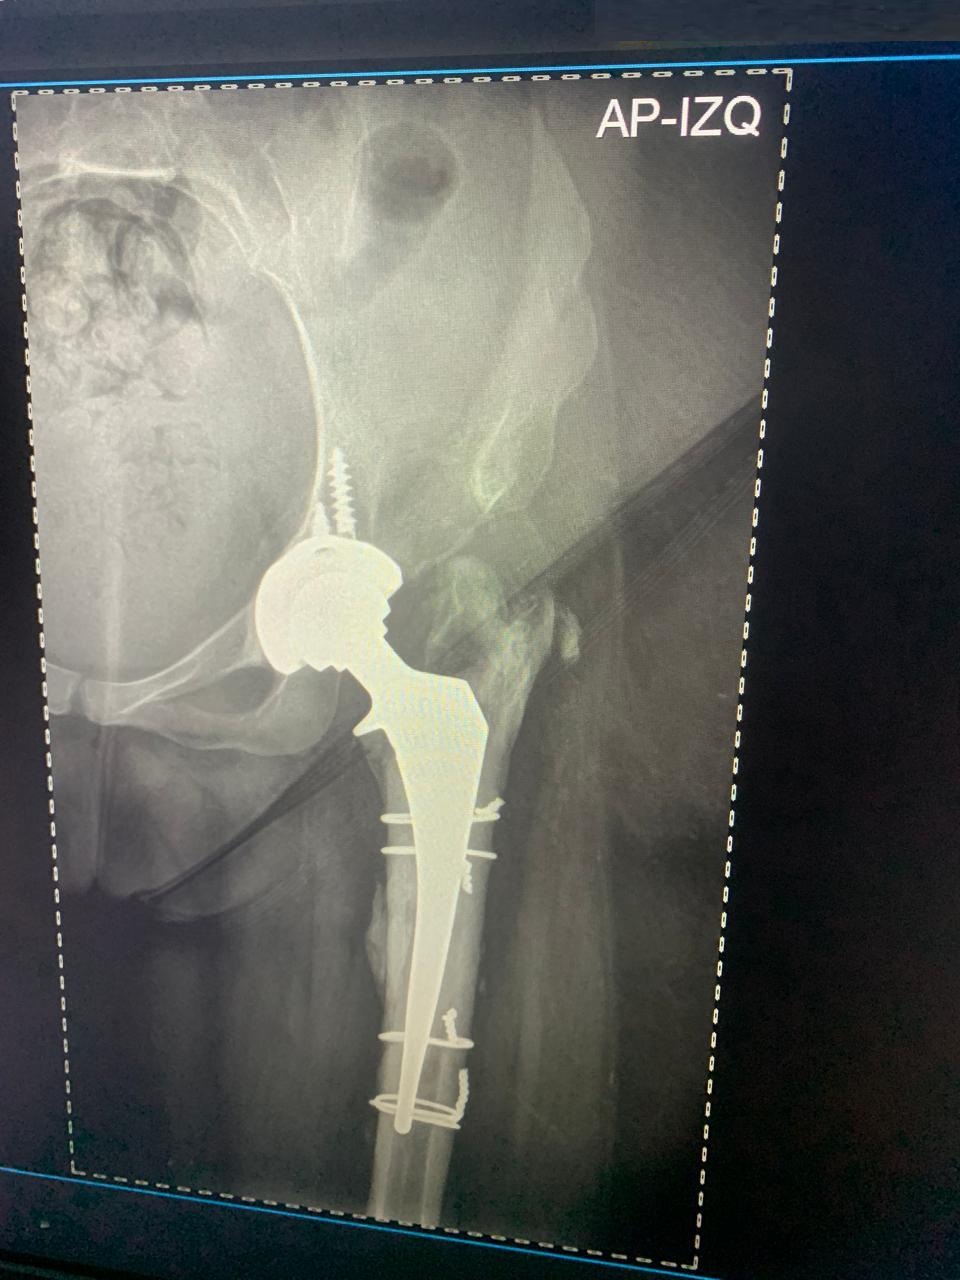

Reemplazo Articular

Artroplastia Total

de Cadera Derecha

• Perfil del Paciente: Femenino, 29 años. Cuadro de dolor severo de larga evolución.

• Diagnóstico: Limitación funcional severa para la marcha y actividades de la vida diaria.

• Procedimiento: Reemplazo total de cadera izquierda.

• Evolución (3 años): Reintegración total a sus actividades con excelente estabilidad y ausencia de dolor.